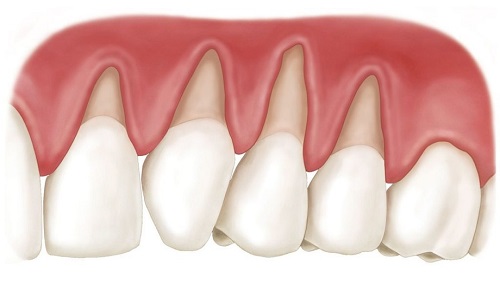

Maintaining dental health requires a structured clinical approach rather than a set of universal tips. According to Professor Alexander von Breuer, sustainable dental outcomes are achieved when prevention is based